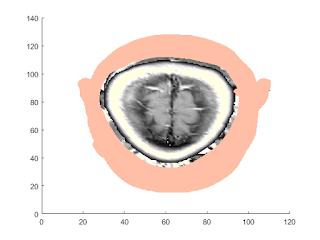

Slices 3-Dimensional MRI Data

load mri;%Load the MRI data figure; montage(D,map) %view the 27 horizontal slices as a montage. title('Horizontal Slices');

M1 = D(:,64,:,:); size(M1);

M2 = reshape(M1,[128 27]); size(M2)

figure; imshow(M2,map);

title('Sagittal - Raw Data');

T0 = maketform('affine',[0 -2.5; 1 0; 0 0]); R2 = makeresampler({'cubic','nearest'},'fill'); M3 = imtransform(M2,T0,R2); figure; imshow(M3,map); title('Sagittal - IMTRANSFORM');

T1 = maketform('affine',[-2.5 0; 0 1; 68.5 0]); inverseFcn = @(X,t) [X repmat(t.tdata,[size(X,1) 1])]; T2 = maketform('custom',3,2,[],inverseFcn,64); Tc = maketform('composite',T1,T2); R3 = makeresampler({'cubic','nearest','nearest'},'fill'); M4 = tformarray(D,Tc,R3,[4 1 2],[1 2],[66 128],[],0); figure; imshow(M4,map); title('Sagittal - TFORMARRAY');

T3 = maketform('affine',[-2.5 0 0; 0 1 0; 0 0 0.5; 68.5 0 -14]); S = tformarray(D,T3,R3,[4 1 2],[1 2 4],[66 128 35],[],0); S2 = padarray(S,[6 0 0 0],0,'both'); figure, montage(S2,map) title('Sagittal Slices'); M1 = D(:,64,:,:); size(M1) M2 = reshape(M1,[128 27]); size(M2) figure, imshow(M2,map); title('Sagittal - Raw Data');